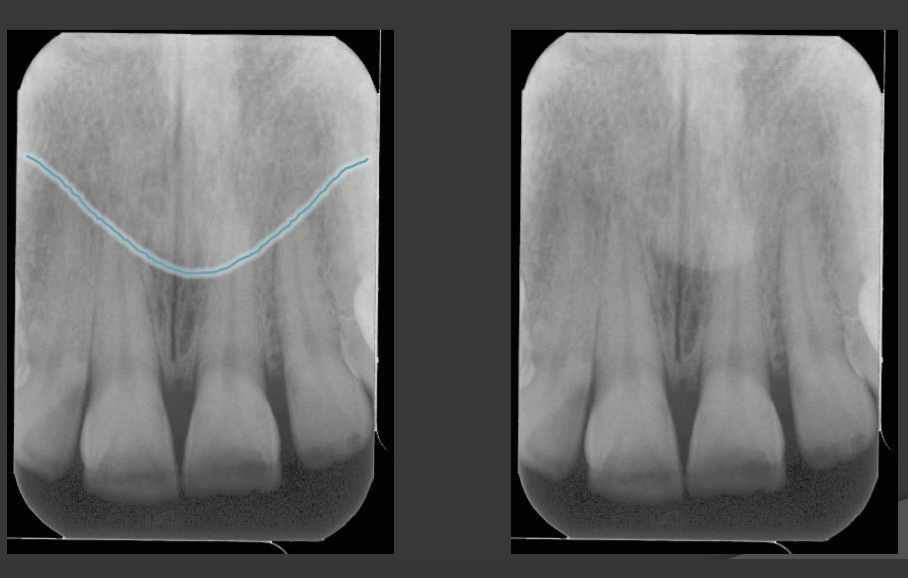

Why do we set a vertical angle when taking radiographs?

To account for the curve of Wilson, where the contacts are tipped 8-10 degrees.